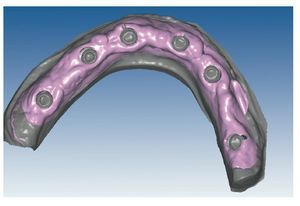

Mediante el uso de un escáner óptico de luz estructurada, los protocolos CAD registran los primeros datos relativos al modelo maestro con las correspondientes posiciones de implante (figs. 87 y 92). En el siguiente paso tiene lugar la digitalización de la planificación, previamente realizada en cera de escaneo matificada, de la restauración definitiva (figs. 88, 90 y 93). La subsiguiente conciliación de los datos mediante el uso del software de diseño dental permite al protésico planificar virtualmente el resto del procedimiento (figs. 89 y 91, 94 a 96) a partir del diseño de las estructuras (figs. 97 y 98).

Figs. 94 a 95. Planificación CAD de la estructura del maxilar inferior, en representación lingual y vestibular.

Figs. 96 a 98. El diseño definitivo de la estructura del maxilar inferior, desde distintas perspectivas.